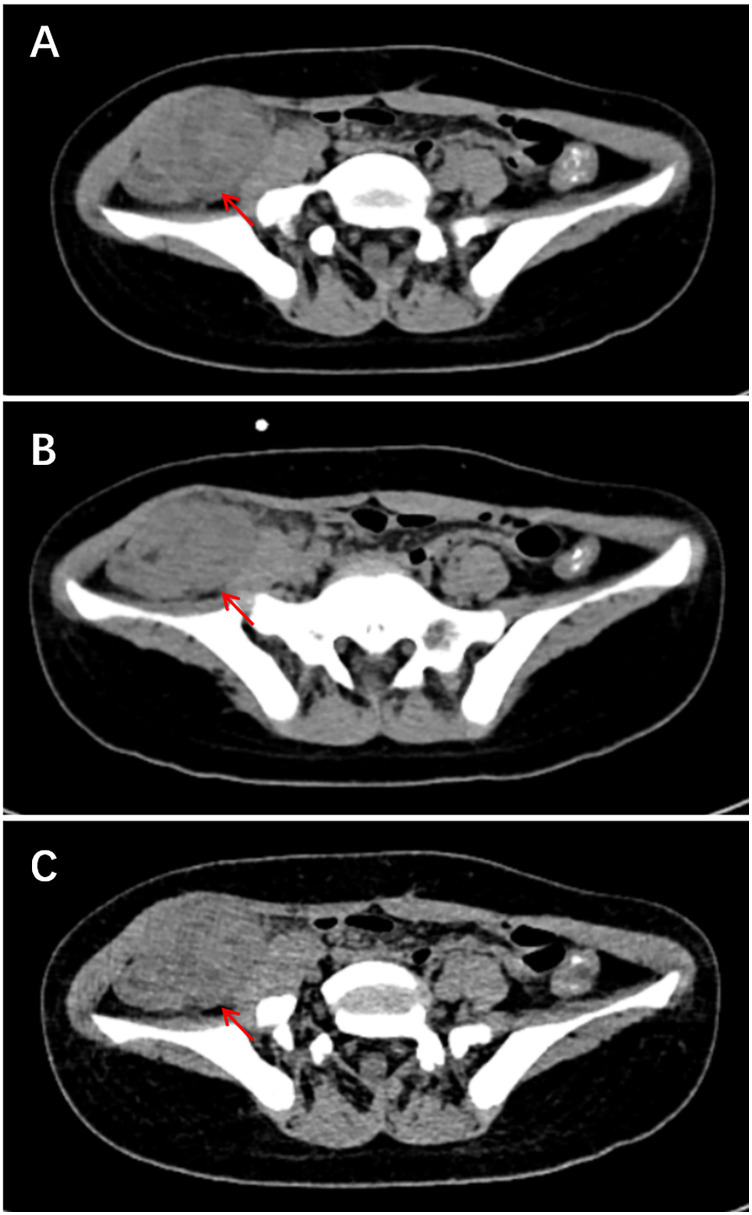

背景:炎性肌纤维母细胞瘤(IMT)是一种罕见的中间恶性潜能间充质肿瘤。虽然其临床病理特征已在成人中描述,但儿科人群的综合数据仍然有限。方法:回顾性分析2016年1月至2024年6月山西省儿童医院诊断为IMT的儿童患者。系统分析临床资料、影像学、组织病理学、免疫组化(IHC)和结果。结果:共纳入16例临床资料及随访资料完整的患者。男性10例,女性6例,中位年龄5.0岁。原发肿瘤部位及临床表现多样:8例位于腹腔及盆腔,表现为腹痛、恶心、呕吐、发热;4例位于头颈部及面部,3例表现为无痛性局部肿块,1例表现为吸气性呼吸困难;胸壁、臀区、左上肢各1例,均表现为无痛性局部肿块;肺部1例,表现为咳嗽、咳痰、反复呼吸道感染。所有16例患者均接受手术治疗;3例局部复发需要再次手术。最后随访中,15例无病,1例在alk靶向治疗下保持稳定。结论:儿童IMT是一种罕见的低级别恶性肿瘤,预后良好。完全手术切除仍然是治疗的基石。alk靶向治疗可使不可切除或复发性疾病的患者受益。由于有复发的危险,需要长期监测。

Results: A total of 16 patients with complete clinical data and follow-up information were included. There were 10 male and 6 female patients, with a median age of 5.0 years. The primary tumor locations and clinical manifestations were diverse: 8 cases were located in the abdominal and pelvic cavities, presenting with abdominal pain, nausea, vomiting, and fever; 4 cases were located in the head, neck, and facial region, with 3 presenting as painless localized masses and 1 with inspiratory dyspnea; 1 case each occurred in the chest wall, gluteal region, and left upper limb, all presenting with painless localized masses; and 1 case occurred in the lung, presenting with cough, sputum, and recurrent respiratory infections. All 16 patients underwent surgery; three developed local recurrence requiring re-operation. At last follow-up, 15 were disease-free and one remained stable on ALK-targeted therapy.